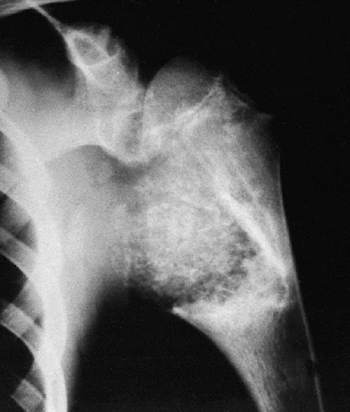

diagnostic. The typical lesion is located in the metaphysis, involves

pattern) (Figs. 14.7 and 14.8).

![]() |

Figure 14.7

Anteroposterior plain radiograph of an 18-year-old man with an osteosarcoma of his proximal tibia. There is increased density in the proximal tibia associated with cortical destruction and extraosseous bone formation. Biopsy was confirmatory. |